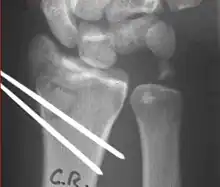

Surgical options have been shown to be successful in patients with unstable extra-articular or minimal articular distal radius fractures. These options include percutaneous pinning, external fixation, and ORIF using plating. Patients with low functional demand of their wrists can be treated successfully with nonsurgical management; however, in more active and fit patients with fractures that are reducible by closed means, nonbridging external fixation is preferred, as it has less serious complications when compared to other surgical options.[4] The most common complication associated with nonbridging external fixation is pin tract infection, which can be managed with antibiotics and frequent dressing changes, and rarely results in reoperation.[4] The external fixator is placed for 5 to 6 weeks and can be removed in an outpatient setting.[4]